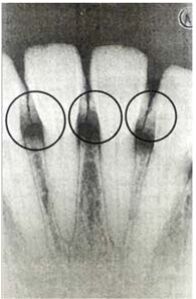

52. 對於下圖圓圈處放射線不透性的影像,最有可能因以下何者所導致?

(A)齒頸部齲齒 (B)牙骨質不全 (C)牙結石 (D)填補材料